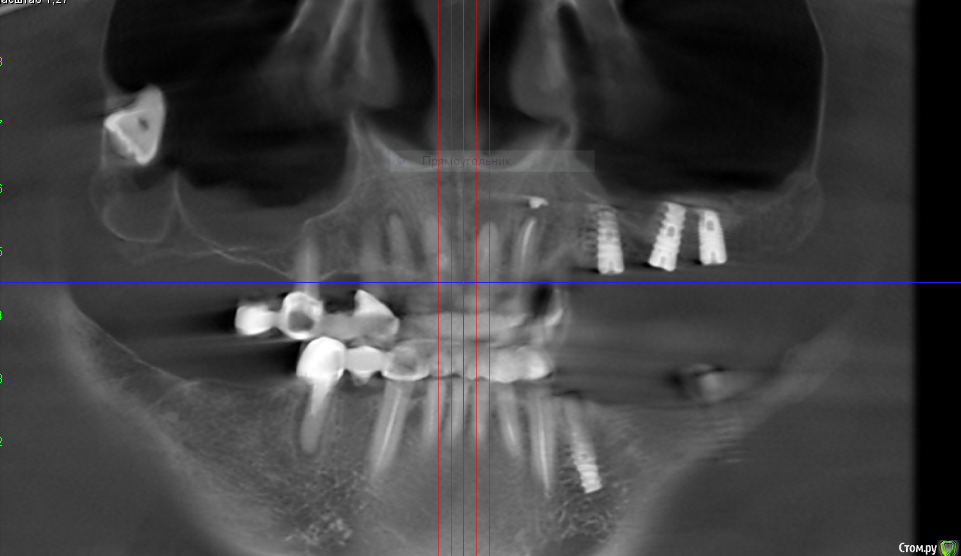

V20 Опубликовано 28 апреля, 2019 Поделиться Опубликовано 28 апреля, 2019 (изменено) Доброго времени суток , помогите пожалуйста разобраться с ситуацией.В мае 2018 года был проведен синус лифтинг с одновременной установкой 3 имплантов, Спустя 5-7 дней на фоне приема антибиотиков(Аугментин), развился левосторонний гайморит. Прошел курс консервативного лечения, пазуха успокоилась.Было решено протезироваться . В феврале 2019 года при откручивании ФД выкрутился имплант (по центру ) и образовался свищ, . Была сделана пластика свища. Сообщение закрылось.На настоящий момент сохраняется чуть заметная припухлость щеки в проекции пазухи и немного поднывает десна.(больше в районе крайнего импланта) На ощупь языком в месте соприкосновения десны и щеки небольшая припухлость ( похоже по проекции разреза).Что интересно с утра десна не болит начинается дискомфорт чуть позже. Уважаемые доктора , помогите пожалуйста в дальнейшей тактике - мнения врачей кардинально расходятся(снимки через неделю после синус лифтинга Снимок 3 месяца назад после консервативного лечения у ЛОРа Последний снимок (2 месяца назад) И еще хотелось бы услышать Ваше мнение о импланте на месте 24 зуба Заранее спасибо. Изменено 28 апреля, 2019 пользователем V20 Ссылка на комментарий

Bier Опубликовано 1 мая, 2019 Поделиться Опубликовано 1 мая, 2019 Я бы раскрыл как при синуслифтинге, чтобы оценить что там такое. По КТ все не очень хорошо. Ссылка на комментарий

V20 Опубликовано 1 мая, 2019 Автор Поделиться Опубликовано 1 мая, 2019 (изменено) Я бы раскрыл как при синуслифтинге, чтобы оценить что там такое. По КТ все не очень хорошо.Доктор, не могли бы вы уточнить что именно нехорошо, просто лечащие стоматологи говорят что кроме синусита все норма... Изменено 1 мая, 2019 пользователем V20 Ссылка на комментарий

Bier Опубликовано 1 мая, 2019 Поделиться Опубликовано 1 мая, 2019 синусит и есть не хорошо. У него есть причина. 1 Ссылка на комментарий